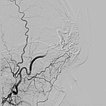

Digital subtraction angiography (DSA) with contrast injection into the right external carotid artery. The superficial temporal artery reveals a microfistulous AVM with markedly dilated feeder arteries on the right forehead with immediate venous outflow.

DSA image depicting the arterial inflow, nidus with small arteriovenous fistulae, and venous outflow of the AVM before embolization. The complete angiomorphology of the AVM, at this point untreated, is easily visible.